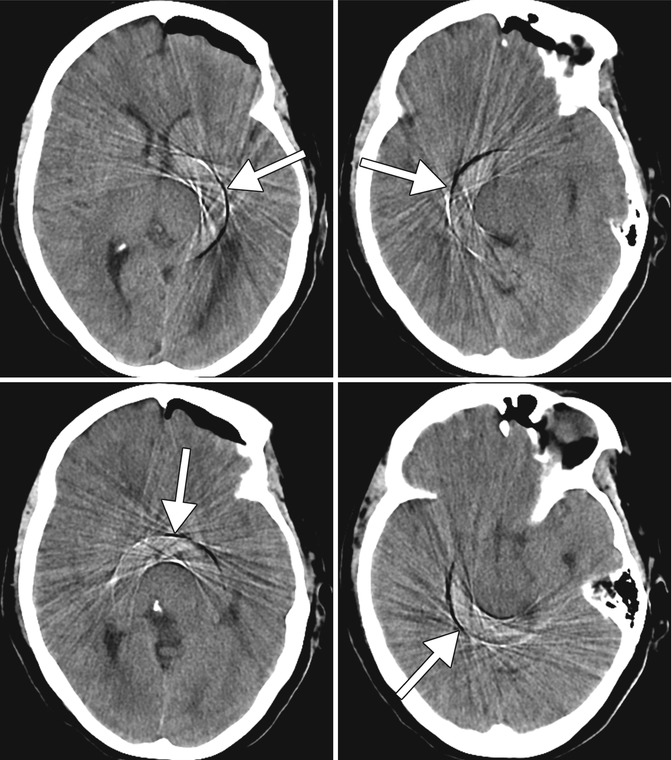

Ct Tube Arcing Artifact . Artifact on two to three consecutive slices of the ct transaxial images of a patient, which showed near‑parallel streaks across the transaxial. Ct artifacts are common and can occur for various reasons. One or more concentric rings in image. Knowledge of these artifacts is important because they can mimic. Ct 37 artifact from tube arcing (frame from animation in presentation)

Ct 37 artifact from tube arcing (frame from animation in presentation) Artifact on two to three consecutive slices of the ct transaxial images of a patient, which showed near‑parallel streaks across the transaxial. Ct artifacts are common and can occur for various reasons. One or more concentric rings in image. Knowledge of these artifacts is important because they can mimic.

Ct Tube Arcing Artifact Ct artifacts are common and can occur for various reasons. Ct 37 artifact from tube arcing (frame from animation in presentation) One or more concentric rings in image. Ct artifacts are common and can occur for various reasons. Knowledge of these artifacts is important because they can mimic. Artifact on two to three consecutive slices of the ct transaxial images of a patient, which showed near‑parallel streaks across the transaxial.